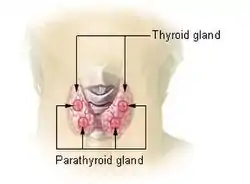

Diagram showing structures in the human neck. The four green shaded areas represent the most common position of the parathyroid glands, which are generally four in number and situated behind the lateral lobes of the thyroid gland (shaded orange). | |

Thyroid and parathyroids as viewed from the front of the neck | |

The parathyroid glands are two pairs of glands usually positioned behind the left and right lobes of the thyroid. Each gland is a yellowish-brown flat ovoid that resembles a lentil seed, usually about 6 mm long and 3 to 4 mm wide, and 1 to 2 mm anteroposteriorly.[1] There are typically four parathyroid glands. The two parathyroid glands on each side which are positioned higher are called the superior parathyroid glands, while the lower two are called the inferior parathyroid glands. Healthy parathyroid glands generally weigh about 30 mg in men and 35 mg in women.[2] These glands are not visible or able to be felt during examination of the neck.[3]